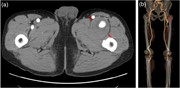

A case of deep femoral artery aneurysm

Hirokuni Ikeda and others

Journal of Surgical Case Reports, Volume 2015, Issue 8, August 2015, rjv111, https://doi.org/10.1093/jscr/rjv111